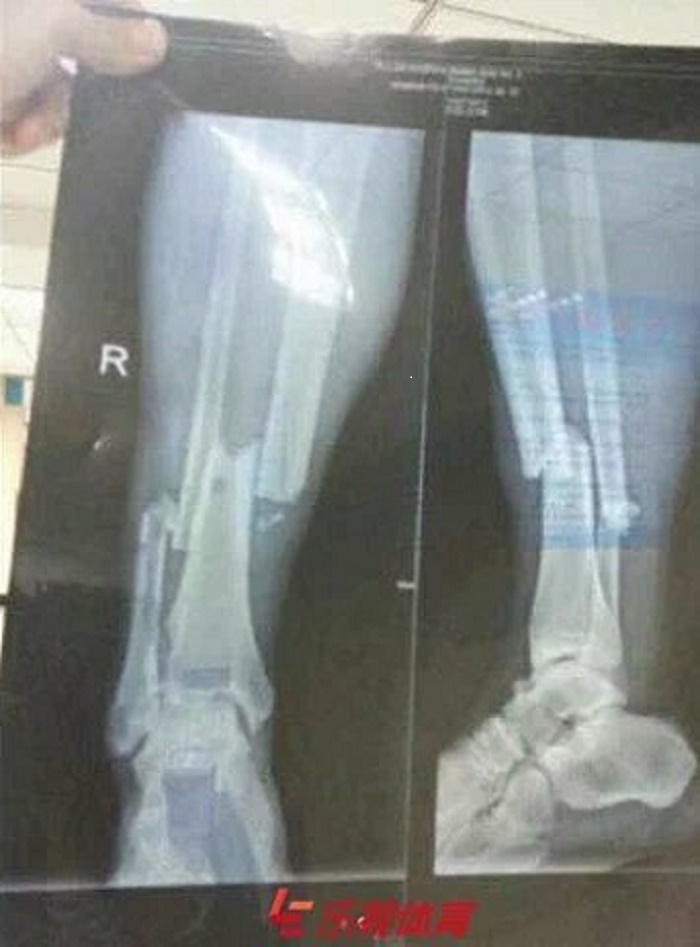

Les médias chinois, très inquiets sur son état, se sont par ailleurs procurés les images de ses radios, qui démontrent la blessure très spectaculaire de Demba Bâ